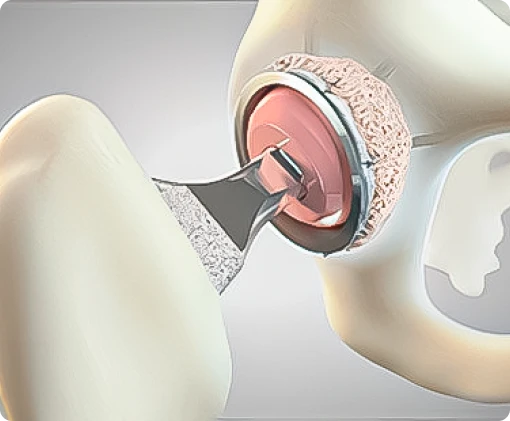

- Quadril

- Revisão de Prótese